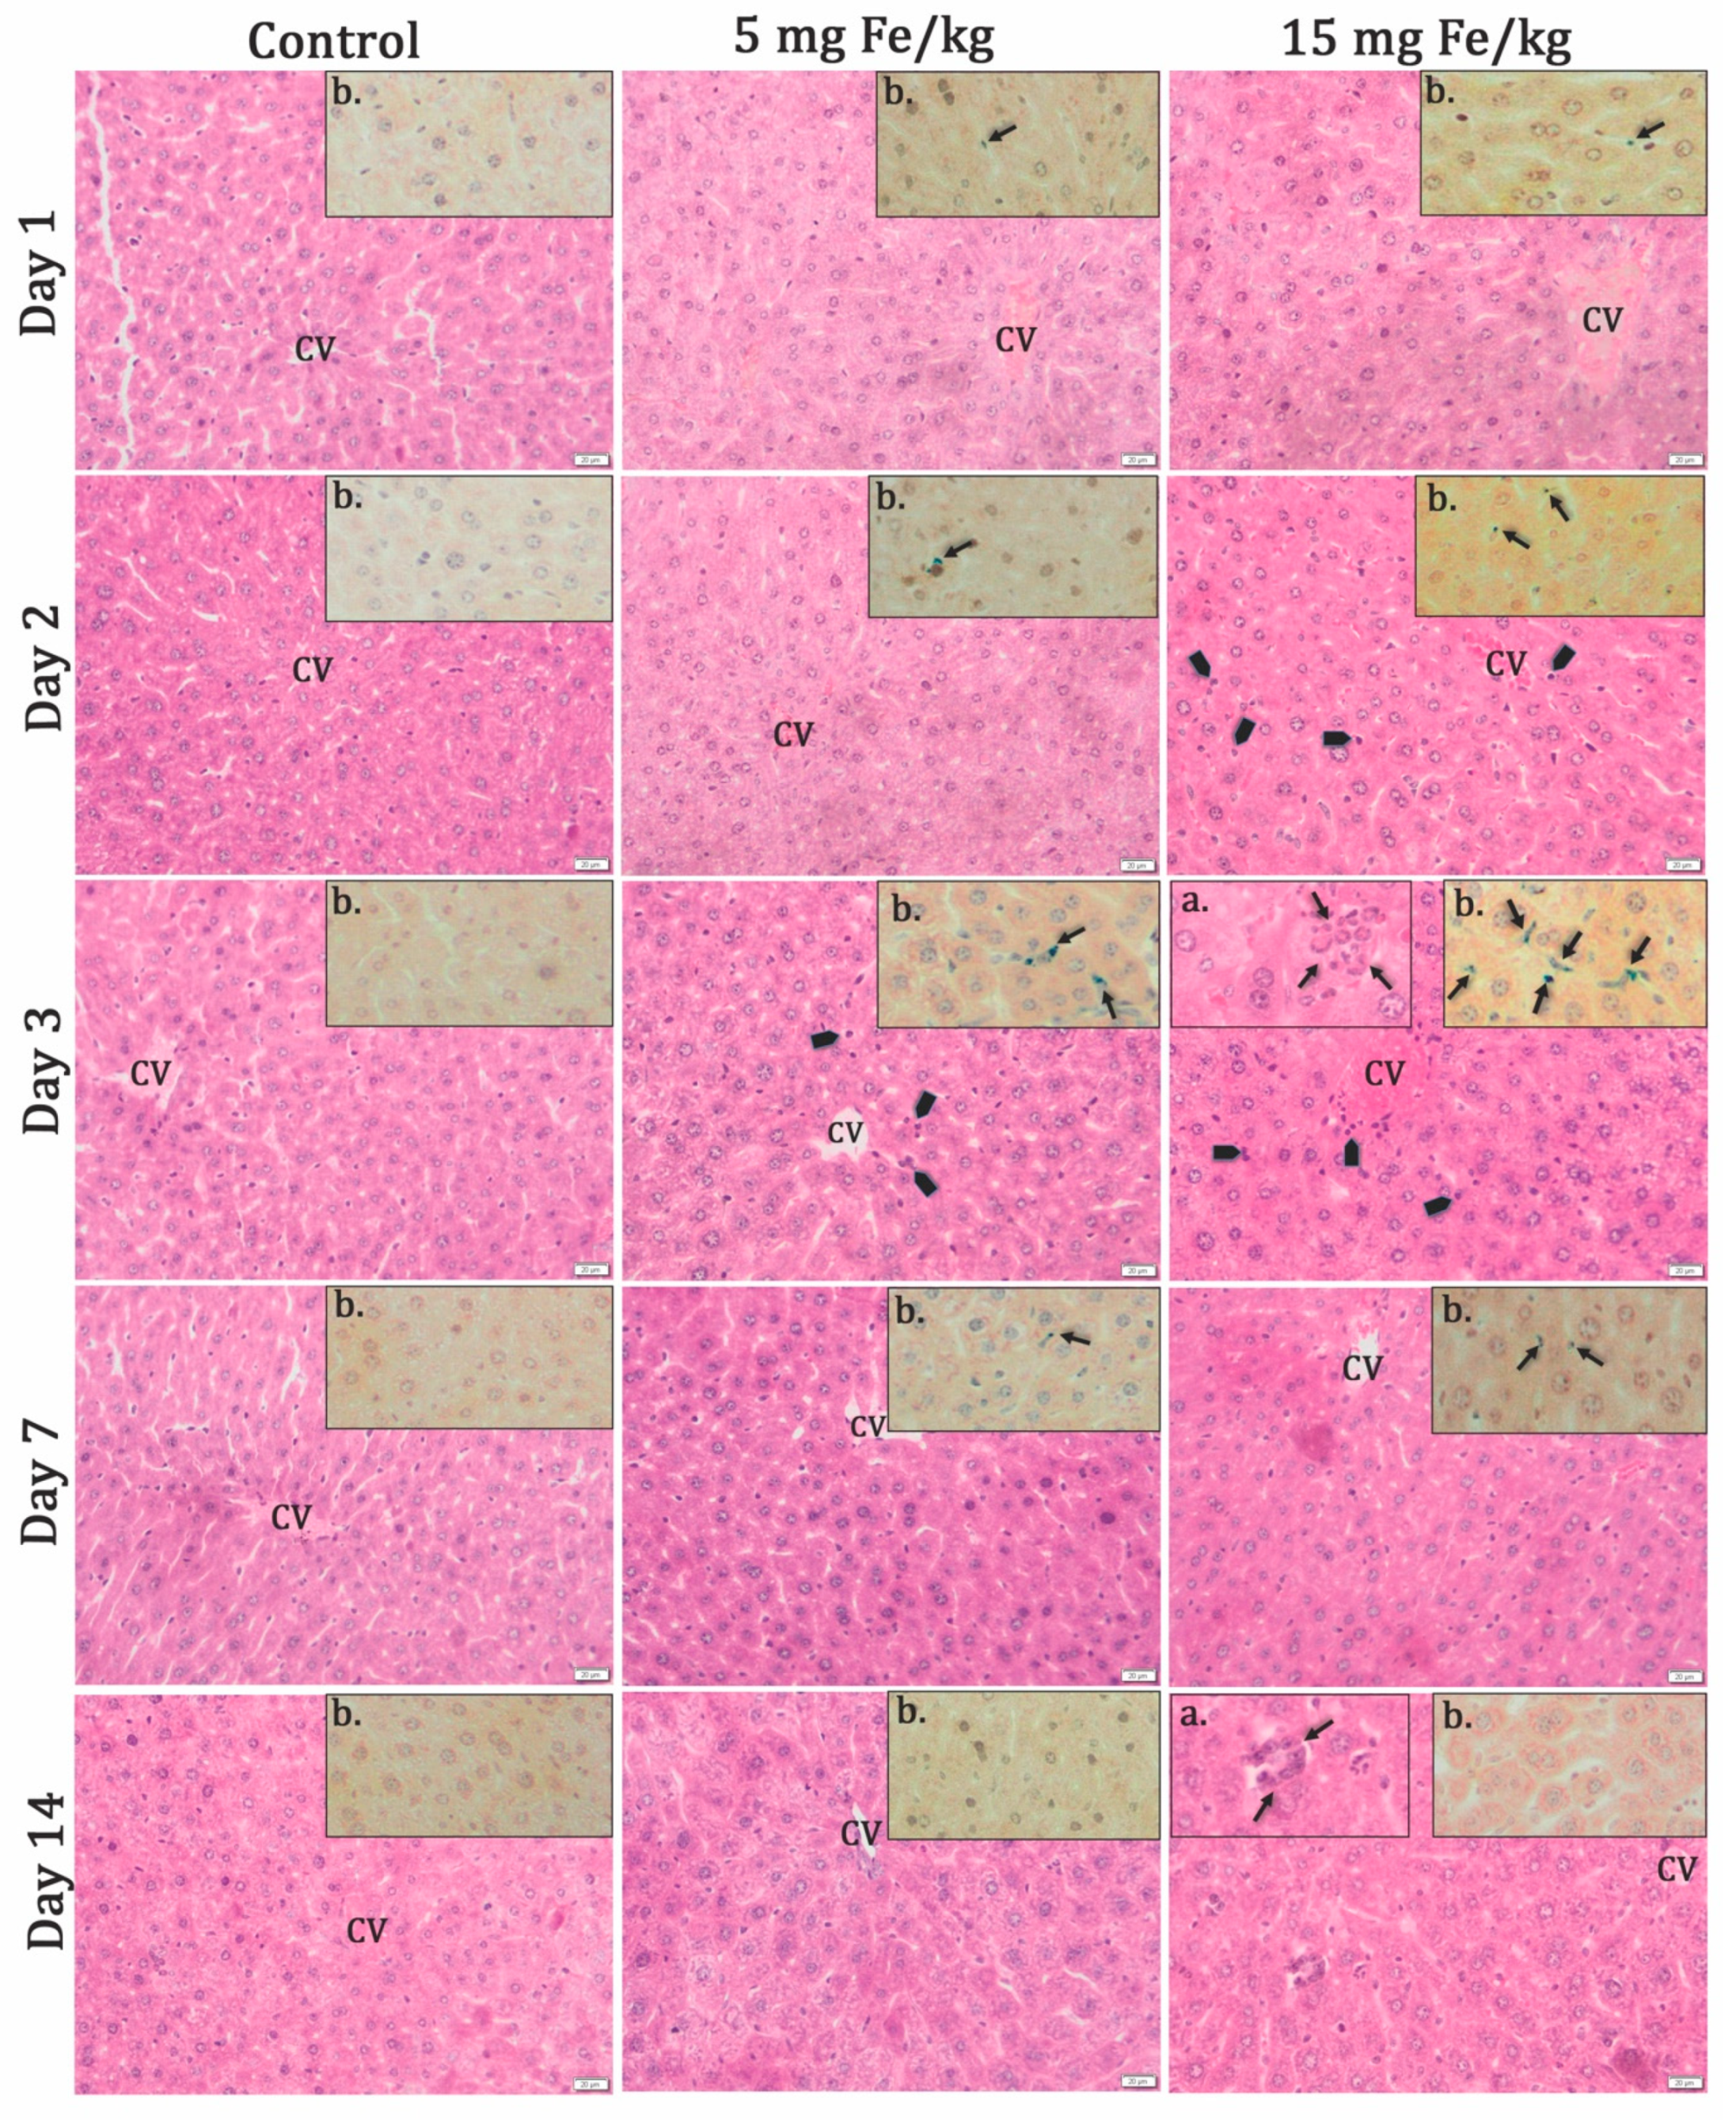

3.2.1. Histochemistry Studies

3.2.2. Relaxometric Studies